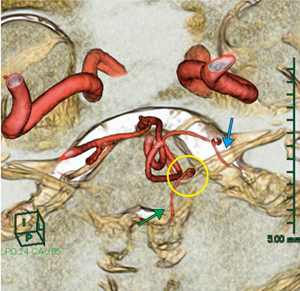

■症例1:脳動脈瘤頸部クリッピング術(70歳代,女性)

MRAにて,左内頸動脈後交通動脈(IC-PC)分岐部に未破裂脳動脈瘤を認めた。脳動脈瘤と動眼神経との位置関係を確認することを目的として画像を作成した。MRA像とHeavy T2強調画像は,撮像日および撮像位置が異なったため,Fusion機能で自動位置合わせを行った。これにより,元画像では把握が困難な血管の走行も立体的に把握できた(図2)。動脈瘤と動眼神経の位置関係を3Dで把握することにより,神経への手技的トラブルを避けることができ,脳動脈瘤頸部クリッピング術前シミュレーションとして有用な画像であった(図3)。

図2 症例1:Heavy T2強調のMPR再構成画像と脳神経Multi Volume画像の比較 |

図3 症例1:脳神経Multi Volume画像 |